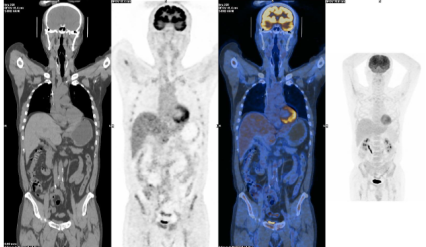

PET-CT复查结果显示,原双侧腋窝淋巴结显示不清;原C7、双侧肱骨、多个胸椎、胸骨、多处肋骨、多个腰椎、骨盆骨、左股骨上段骨质破坏已不明显,PET示代谢较前明显降低(Deauville 3分);原回肠肠壁增厚已不明显;原左臀及左大腿根部骨骼肌肉内多发结节异常放射性浓缩影已不明显,疗效评估达到CR。

上. 基线PET-CT;

下. 塞利尼索联合地西他滨和R-Gemoxd 2疗程后PET-CT